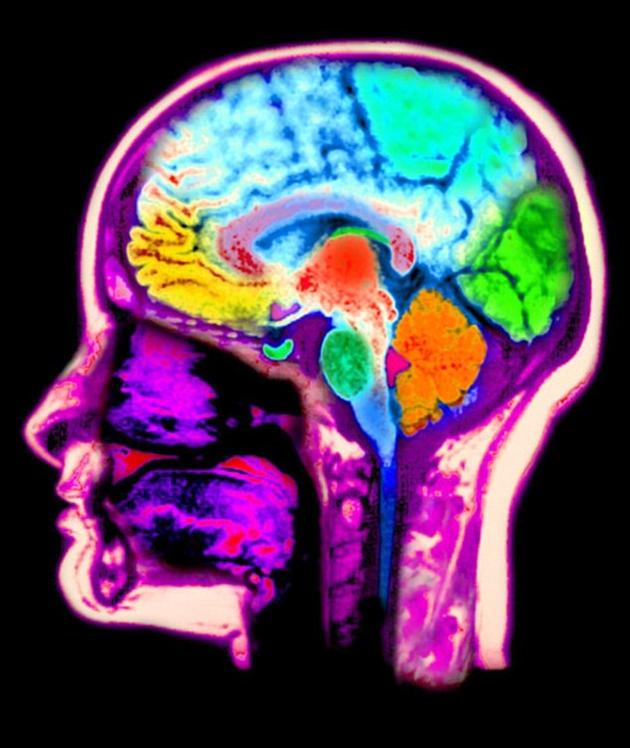

功能核磁共振成像扫描的结果显示,实验中志愿者大脑的中央内凹陷的区域——称为“岛叶皮质”,与意识、感知和保持身体功能在背景中照常运行有关——出现了血流量增加的情况。